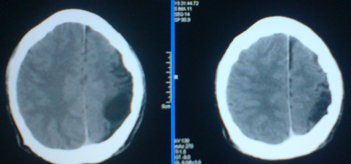

标题: CT24297:患者,男,左手抽搐致摔倒,平时无不适。 [打印本页]

标题: CT24297:患者,男,左手抽搐致摔倒,平时无不适。

1)左侧颞顶叶脑萎缩。2)左侧外侧裂池蛛网膜囊肿?

1.左侧顶叶脑软化并脑脑穿通畸形,左侧大脑半球萎缩。2.左侧外侧裂蛛网膜囊肿。

1、左侧颞顶叶脑软化灶。2、左侧大脑半球萎缩。没有其他病史吗?

左颞顶叶脑萎缩,左外侧裂蛛网膜囊肿。

先天性发育不良

颜面血管瘤? 胼胝体发育不全。